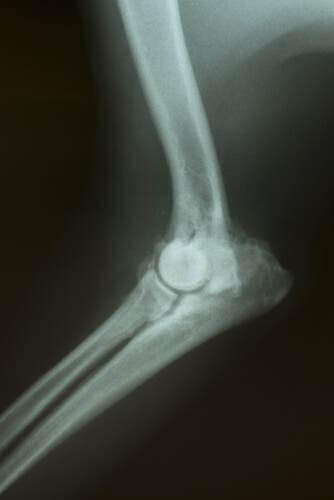

A osteoartrite canina é uma doença que afeta as articulações gradualmente. Ou seja, ela piora com o tempo. Geralmente, é congênita (herdada) e causa uma diminuição da cartilagem, o que provoca dor ou desconforto quando os ossos fazem certos movimentos.

As articulações de um cachorro com osteoartrite são menos flexíveis e mais finas do que as de um cachorro saudável. Se a estrutura da cartilagem é perdida ou desgastada, toda vez que o animal se move, ele sente dor ou incômodo.